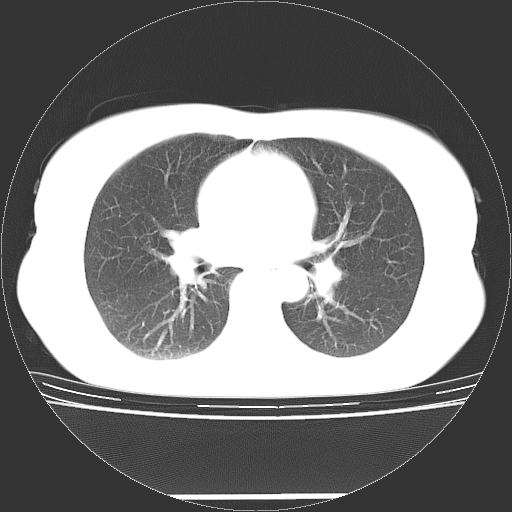

标题: CT27224:女,43岁,体检发现左肺下叶结节影。 [打印本页]

女,43岁,体检发现左肺下叶结节影。

左下肺外带胸膜下见孤立实性均匀密度结节影,边缘光整,增强呈渐进性强化,病灶吴分叶征及毛刺征象;支持硬化性血管瘤。

左肺下叶基底段圆形结节,多考虑:错构瘤>硬化性血瘤>炎症假瘤>周围性肺癌!期待结果!

左肺下叶外侧基底段圆形结节,多考虑:错构瘤>硬化性血瘤>炎症假瘤>周围性肺癌!期待结果!

良性结节,有钙化,强化不明显,考虑软骨性错构瘤。

左肺下叶外基底段良性结节(错构瘤?)。